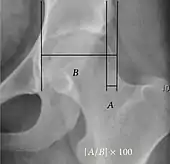

Acetabular depth ratio Deepness of acetabulum.

• The width is measured between the inferior margin of the teardrop and the lateral rim of the acetabulum.[11]

• The depth is measured perpendicularly from the midpoint of the width line.[11]

>250

• Less indicates a dysplastic hip